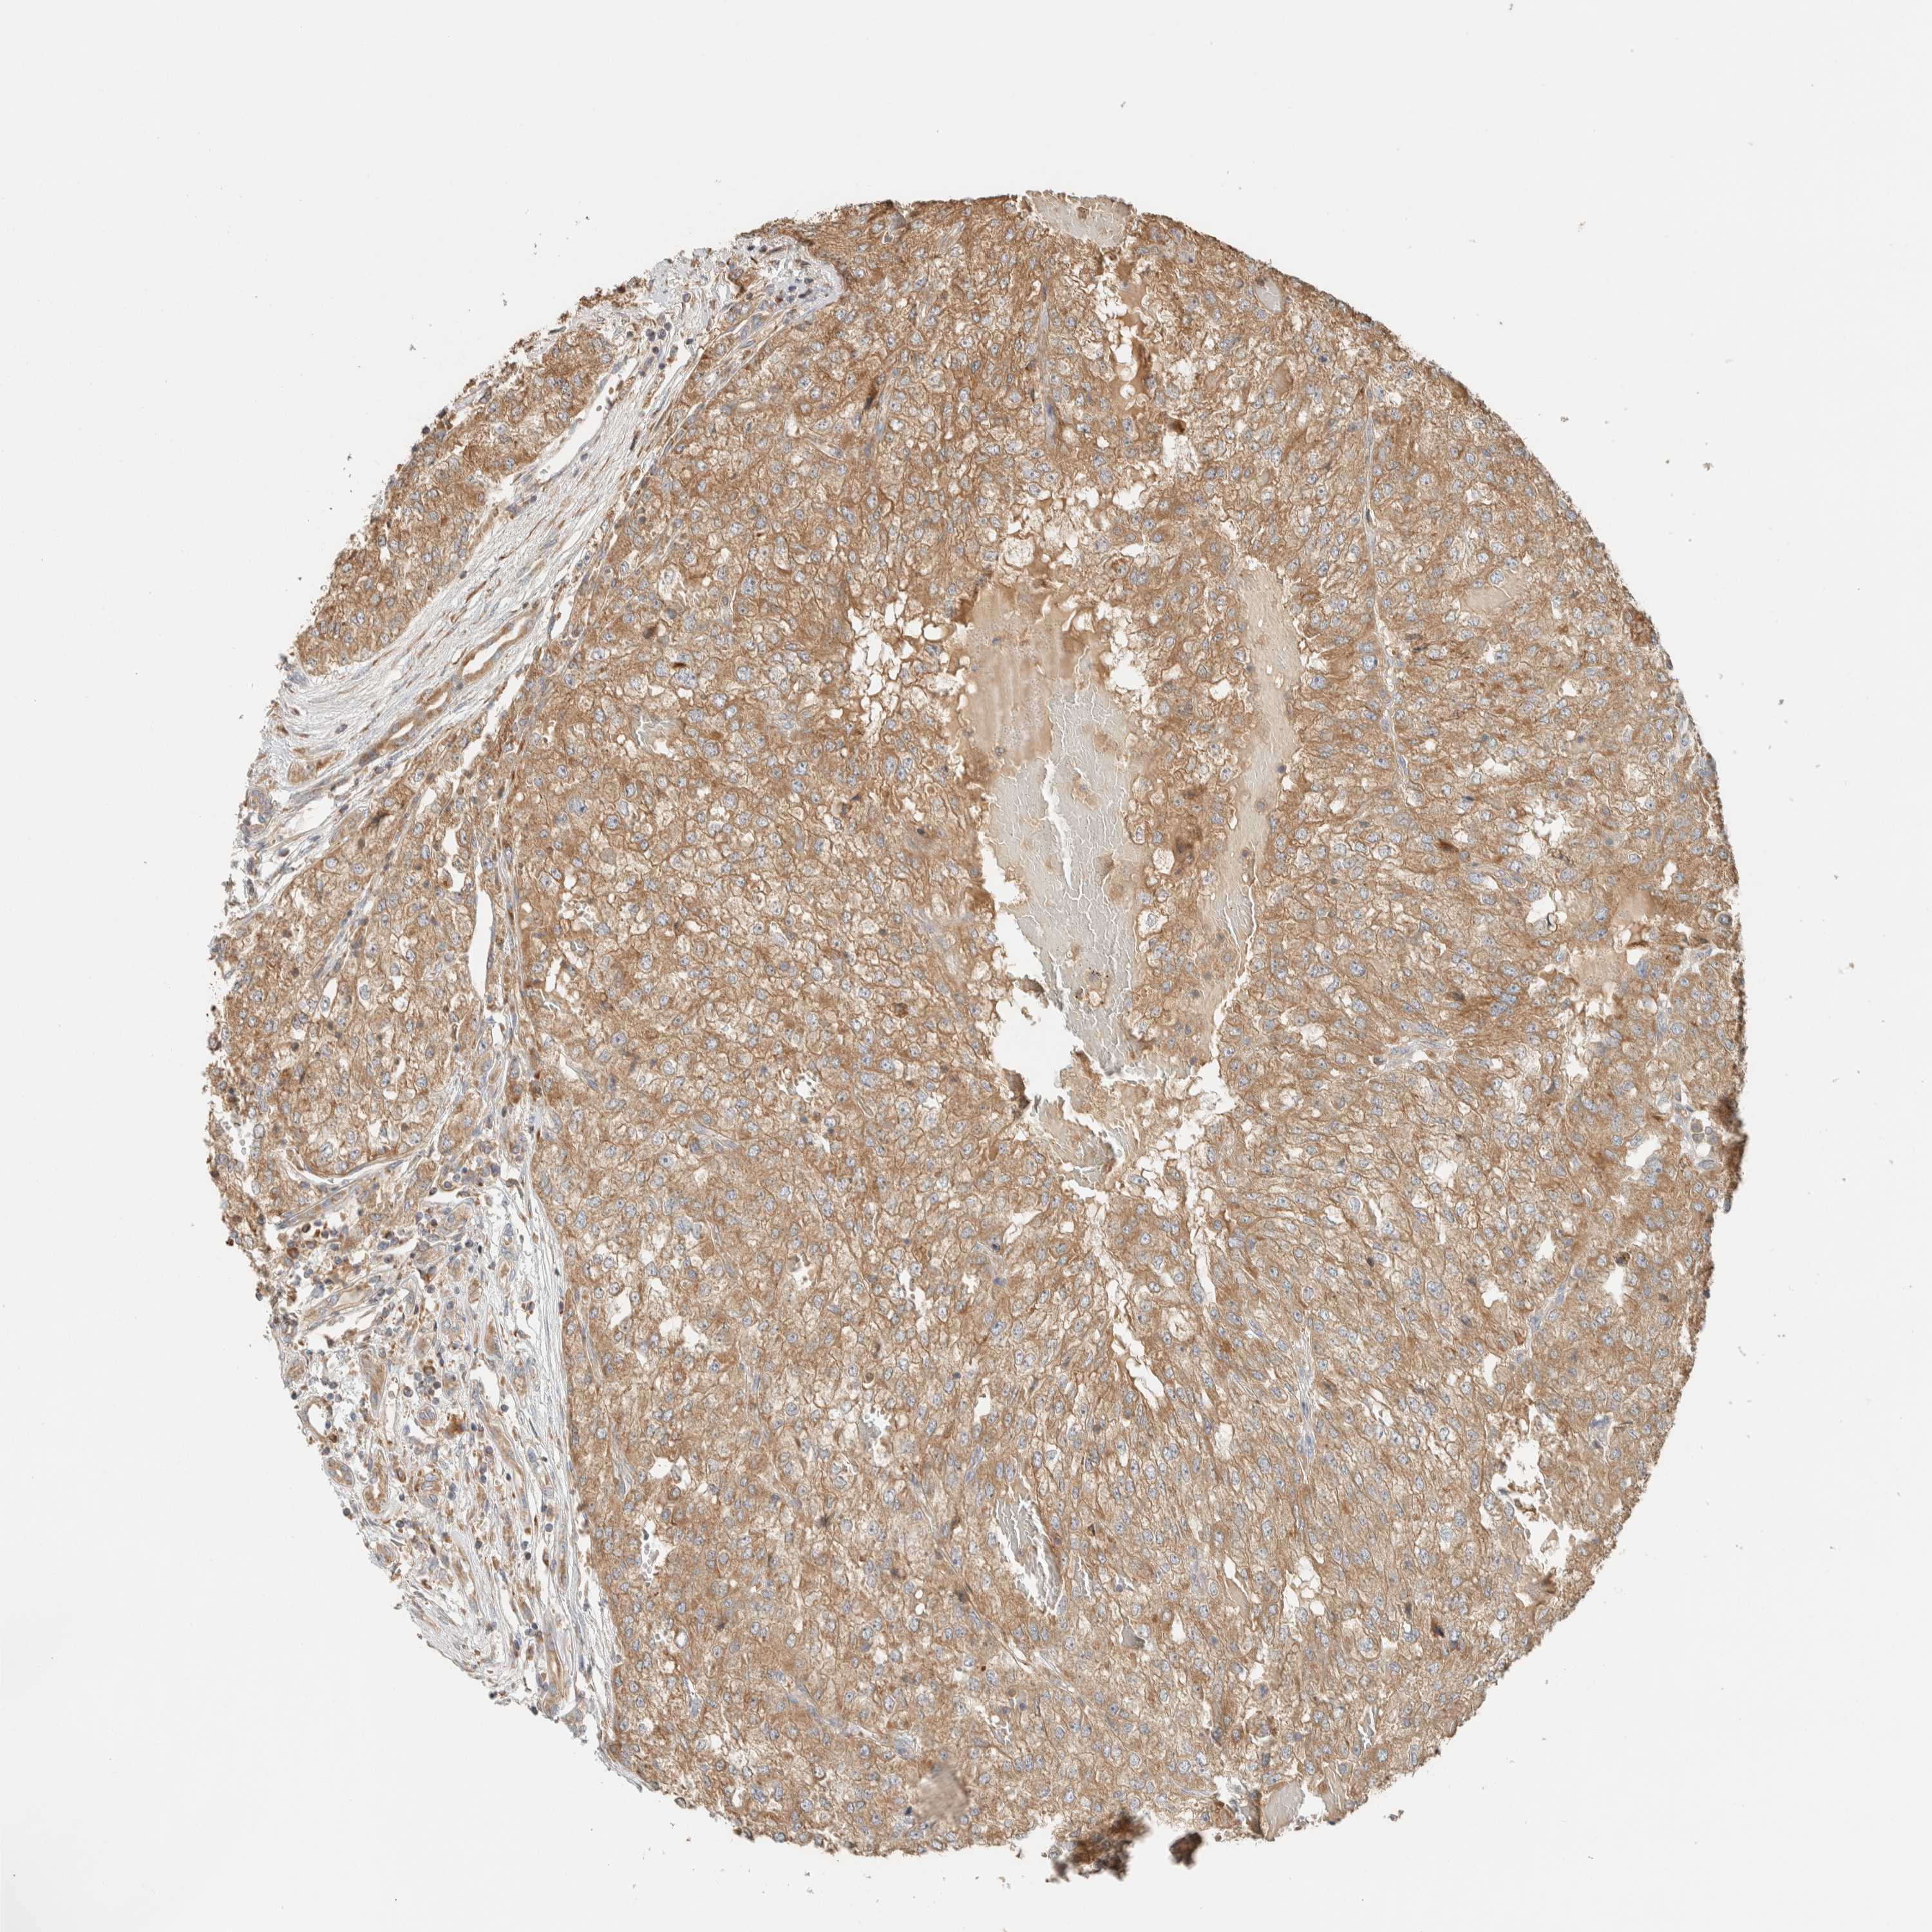

KIDNEY RENAL CLEAR CELL CARCINOMA (VALIDATION) - Interactive survival scatter ploti

The Survival Scatter plot shows the clinical status (i.e. dead or alive) for all individuals in the patient cohort, based on the same data that underlies the corresponding Kaplan-Meier plots. Patients that are alive at last time for follow-up are shown in blue and patients who have died during the study are shown in red.

The x-axis shows the expression levels (FPKM) of the investigated gene in the tumor tissue at the time of diagnosis. The y-axis shows the follow-up time after diagnosis (years). Both axes are complimented with kernel density curves demonstrating the data density over the axes. The top density plot shows the expression levels (FPKM) distribution among dead (red) and alive patients (blue). The right density plot shows the data density of the survived years of dead patients with high and low expression levels respectively, stratified using the cutoff indicated by the vertical dashed line through the Survival Scatter plot. This cutoff is automatically defined based on the FPKM cutoff that minimizes the p-score. The cutoff can be changed by dragging the vertical line or by entering a cutoff value in the square labeled "Current cut-off".

Under the Survival Scatter plot the p-score landscape (black curve; left axis) is shown together with dead median separation (red curve; right axis). Dead median separation is the difference in median mRNA expression between patients who have died with high and low expression, respectively. It is calculated as follows: median FPKM expression of dead patients with high expression - median FPKM expression of dead patients with low expression. This is intended to aid the user in visually exploring custom cutoffs and the associated p-scores and dead median separation.

Individual patient data is displayed and can be filtered by clicking on one or more of the category buttons on the top of the page. Categories describing expression level and patient information include: high, low, alive, dead, female, male and tumor stages. The scale of the x-axis can be toggled between linear and log-scale by clicking on the "x log" button. Mouse-over function shows TCGA ID, patient information and mRNA expression (FPKM) for each patient.

& Survival analysisi

Kaplan-Meier plots summarize results from analysis of correlation between mRNA expression level and patient survival. Patients were divided based on level of expression into one of the two groups "low" (under cut off) or "high" (over cut off). X-axis shows time for survival (years) and y-axis shows the probability of survival, where 1.0 corresponds to 100 percent.

RAB11FIP1 is not prognostic in Kidney Renal Clear Cell Carcinoma (validation)

Best expression cut offi

Based on the FPKM value of each gene, patients were classified into two groups and association between prognosis (survival) and gene expression (FPKM) was examined. The best expression cut-off refers the FPKM value that yields maximal difference with regard to survival between the two groups at the lowest log-rank P-value. Best expression cut-off was selected based on survival analysis .

When clicking on this number, the vertical dashed line indicating cut-off, the interactive survival plot, and the Kaplan-Meier curve will be adjusted to show results based on the best expression cut-off.

: 16.44

P scorei

Log-rank P value for Kaplan-Meier plot showing results from analysis of correlation between mRNA expression level and patient survival.

N/A

5-year survival highi

5-year survival for patients with higher expression than the expression cutoff.

For melanoma and glioma, 3-year survival is shown.

5-year survival lowi

5-year survival for patients with lower expression than the expression cutoff.

TCGA RNA samplesi

RNA-seq data is reported as average FPKM (number Fragments Per Kilobase of exon per Million reads), generated by the The Cancer Genome Atlas (TCGA) .

Normal distribution across the dataset is visualized with box plots, shown as median and 25th and 75th percentiles. Points are displayed as outliers if they are above or below 1.5 times the interquartile range. FPKM values of the individual samples are presented next to the box plot.

Average pTPM 18.3

Number of samples 100